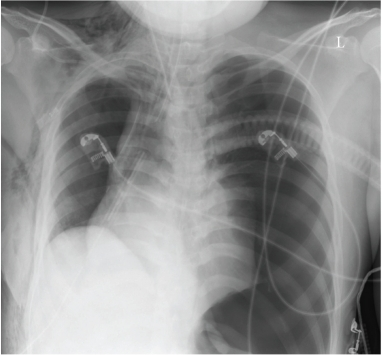

Acute tension pneumothorax following cardiac herniation after pneumonectomy. Steinmann D, Rohr E, Kirschbaum A - Case Rep Med (2010) Bottom Line: A tension pneumothorax is one of the main causes of cardiac arrest in the initial postoperative period after thoracic surgery.Tension pneumothorax and cardiac herniation must be taken into account in hemodynamically unstable patients after pneumonectomy.We report an unusual case of successful treatment of acute tension pneumothorax following cardiac herniation and intrathoracic bleeding after pneumonectomy. View Article: PubMed Central - PubMed Affiliation: Department of Anaesthesia and Critical Care Medicine, University Hospital Freiburg, Hugstetter Strasse 55, 79106 Freiburg, Germany.